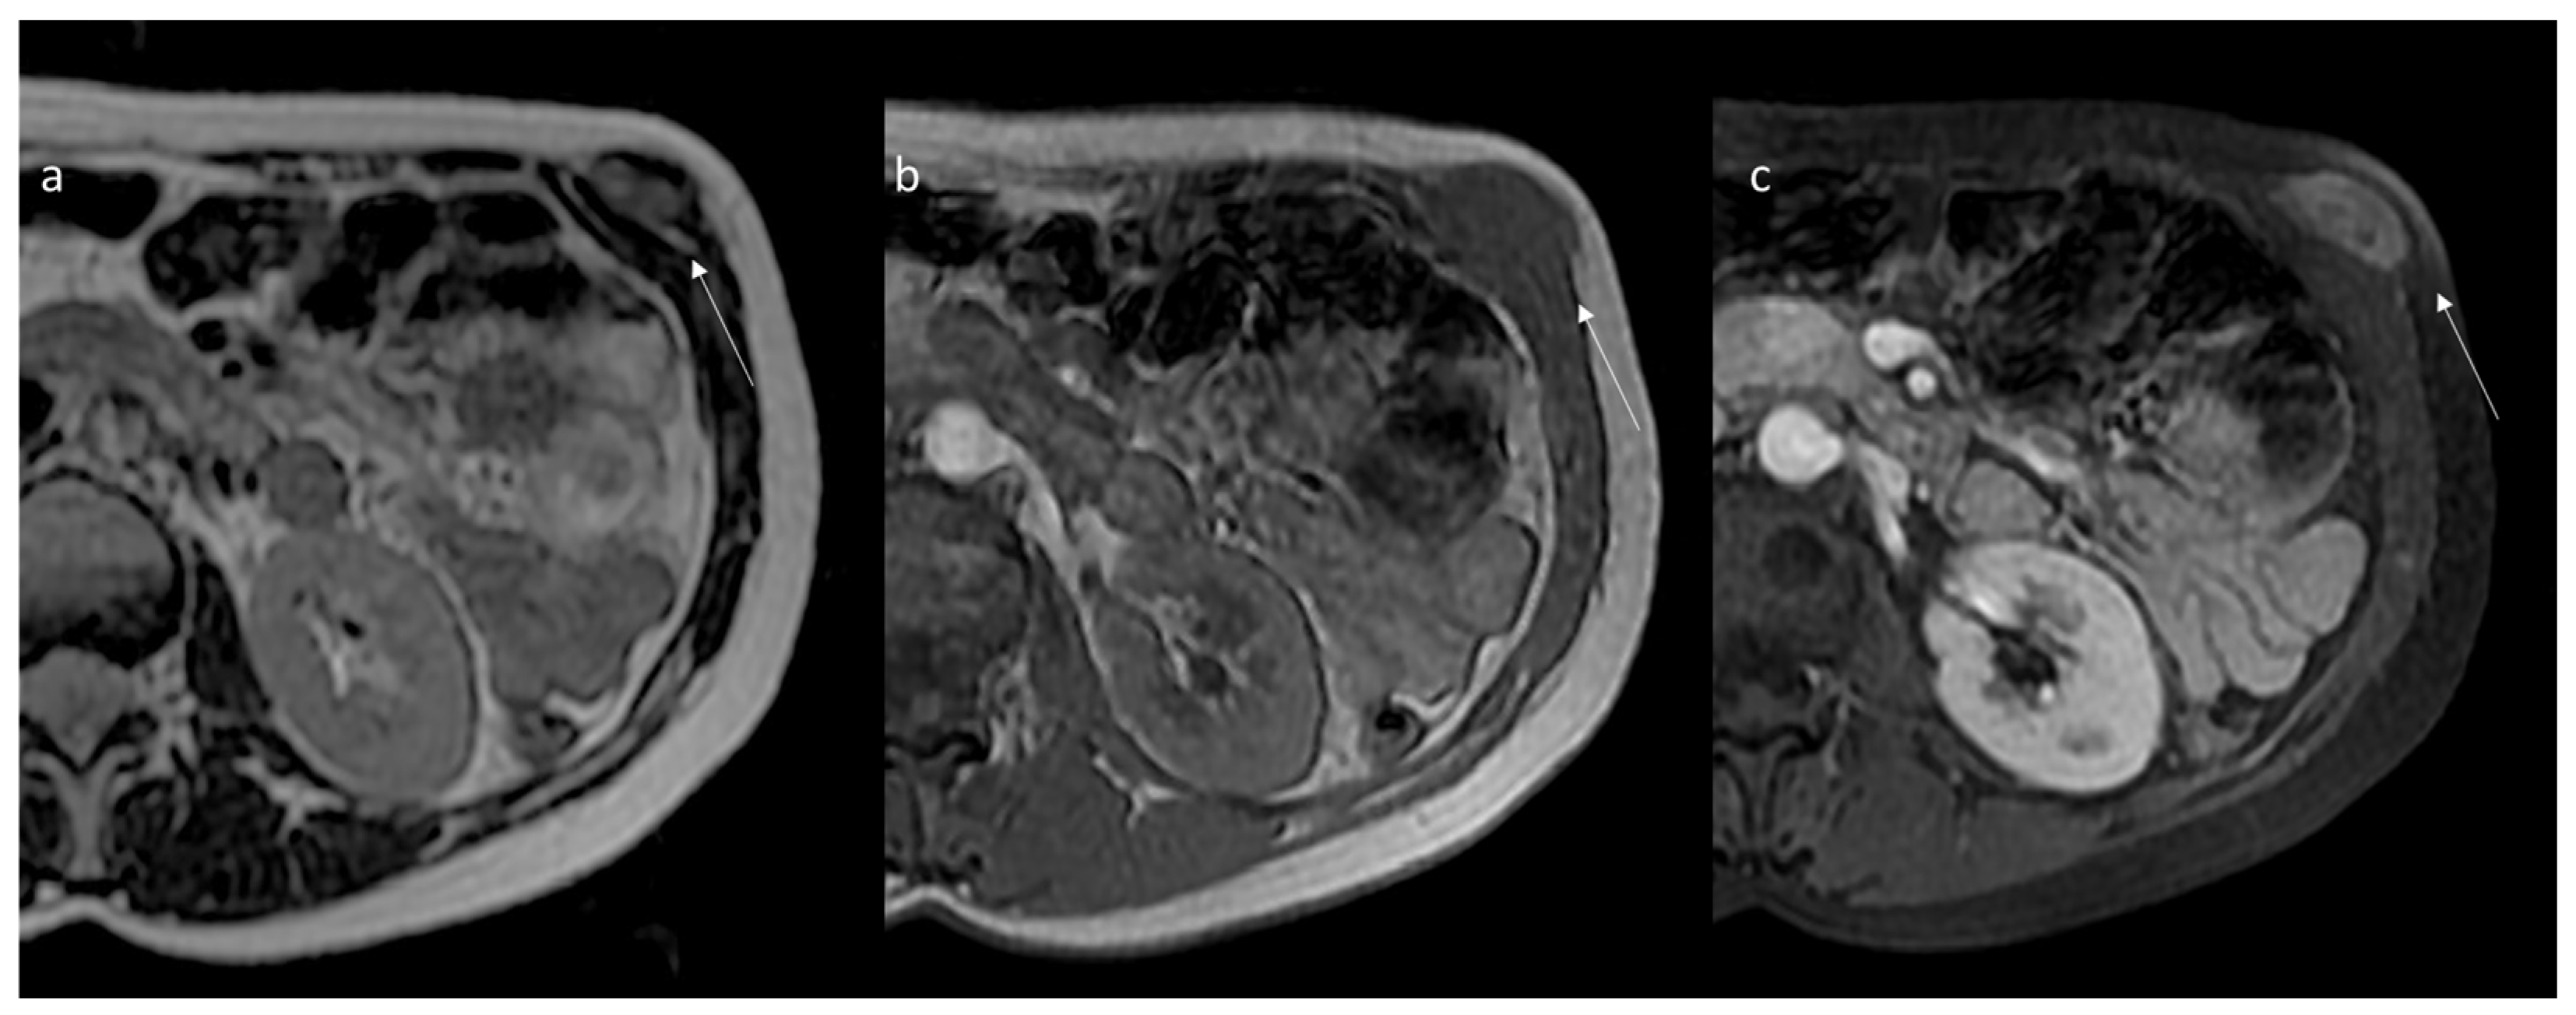

7. Magnetic Resonance Imaging Assessment